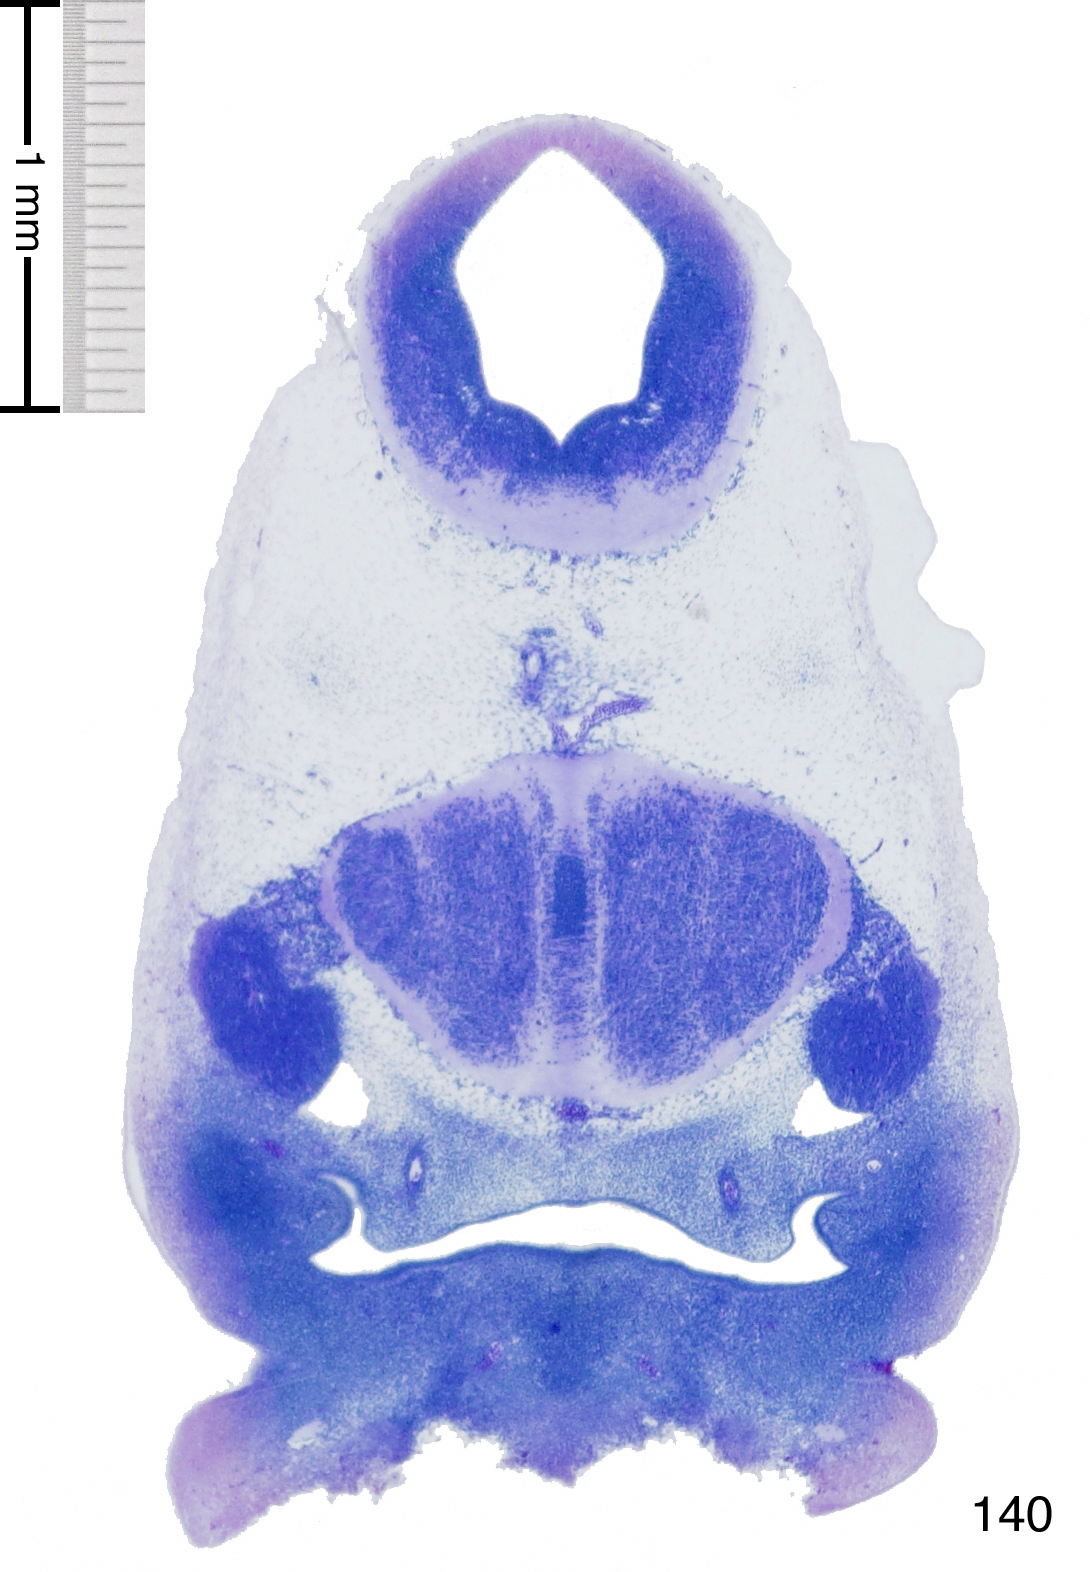

Slides from U. Schambra, coronal cuts with slides at every 5th section, with a hematoxylin and eosin (H & E) stain

More information about this section will be added by U. Schambra at a later date, for now only the images themselves are available..

Currently on section 140.